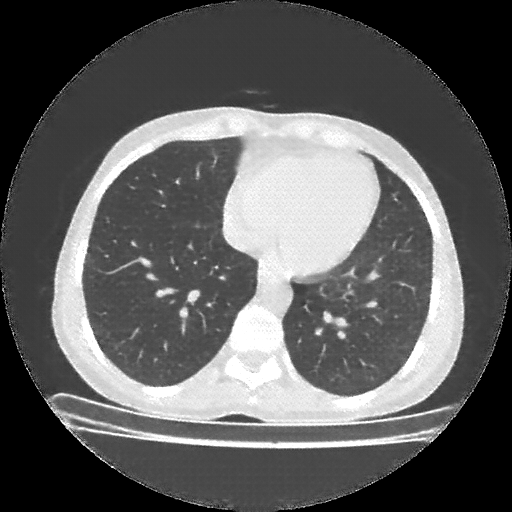

Targeted Slice 70 - Network-Normalized Analysis (Generated vs Real Venous)

0.795

SSIM Score

0.120

RMSE

0.067

MAE

Targeted Slice 70 - HU-Space Analysis (Generated vs Real Venous)

HU SSIM

119.9

HU RMSE

66.7

HU MAE

Generated VENOUS CT scan (A→B translation)

No window - Raw intensity values

Lung window (WL -600, WW 1500 β†’ Low βˆ’1350, High +150)